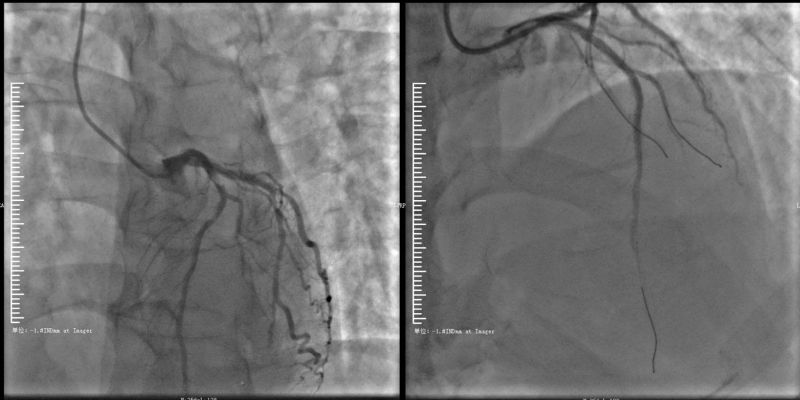

接到转运患者后,烟台山医院急诊科迅速完善心电图检查,确认“急性广泛前壁、高侧壁心肌梗死”诊断后,第一时间联系心内科重症监护病房(CCU)并启动导管室。时间就是心肌,时间就是生命,医护人员紧急将患者送至导管室,10分钟完成急诊冠脉造影术,造影结果显示患者心脏最主要的两支血管“前降支”及“回旋支”几近闭塞,估计心肌梗死面积超过心脏面积的40%。郭方明主任医师20分钟就将血管开通,患者胸痛症状明显缓解。术后将患者转入CCU密切监护,在升压药物难以维持患者血压,且患者出现心力衰竭症状时,郭方明立即决定在床旁植入主动脉内球囊反搏(IABP)以增加心脏血供、维持血压并改善心衰症状。在医护人员的悉心照料下,患者目前已转危为安,生命体征平稳。

血管开通前 血管开通后